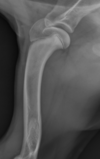

What is shown in these radiographs?

lamellated periosteal reaction